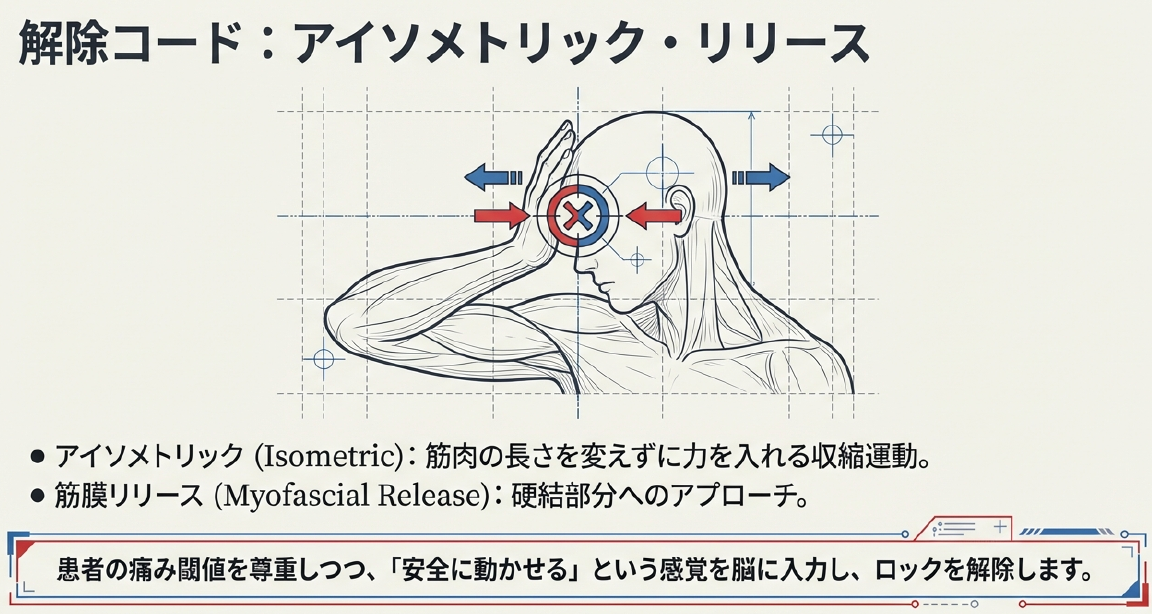

治療の原則は、炎症フェーズの評価に基づく使い分けです。急性期直後であれば、冷却で代償性炎症を抑えつつ、早期に温熱を加えて血流を促します。温熱は筋衛星細胞の活性化を助け、修復を加速させる点で理にかなっています。手技療法では、硬結のアイソメトリックなリリースや、筋膜リリースが有効で、患者の痛み閾値を尊重しつつ「安全に動かせる」感覚を植え付けます。理学療法として、牽引は椎間圧を軽減し、軽い頚部等速運動は固有受容器を刺激して抑制反射を呼び込みます。実際の臨床では、痛みの10%以内の範囲で自動運動を導入すると、再発率が有意に低下するというデータが支持しています。薬理的にはNSAIDsが第一選択ですが、胃腸リスクを考慮し短期使用に留めます。